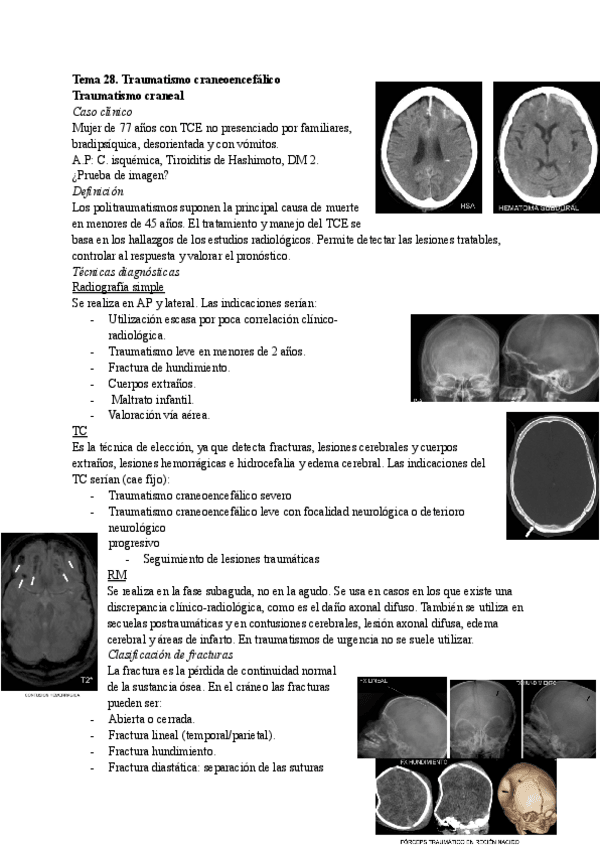

tema-28-traumatismo-craneoencefalico.pdf

tema-28.pdf

Tema-28.-Traumatismo-craneoencefalico.pdf